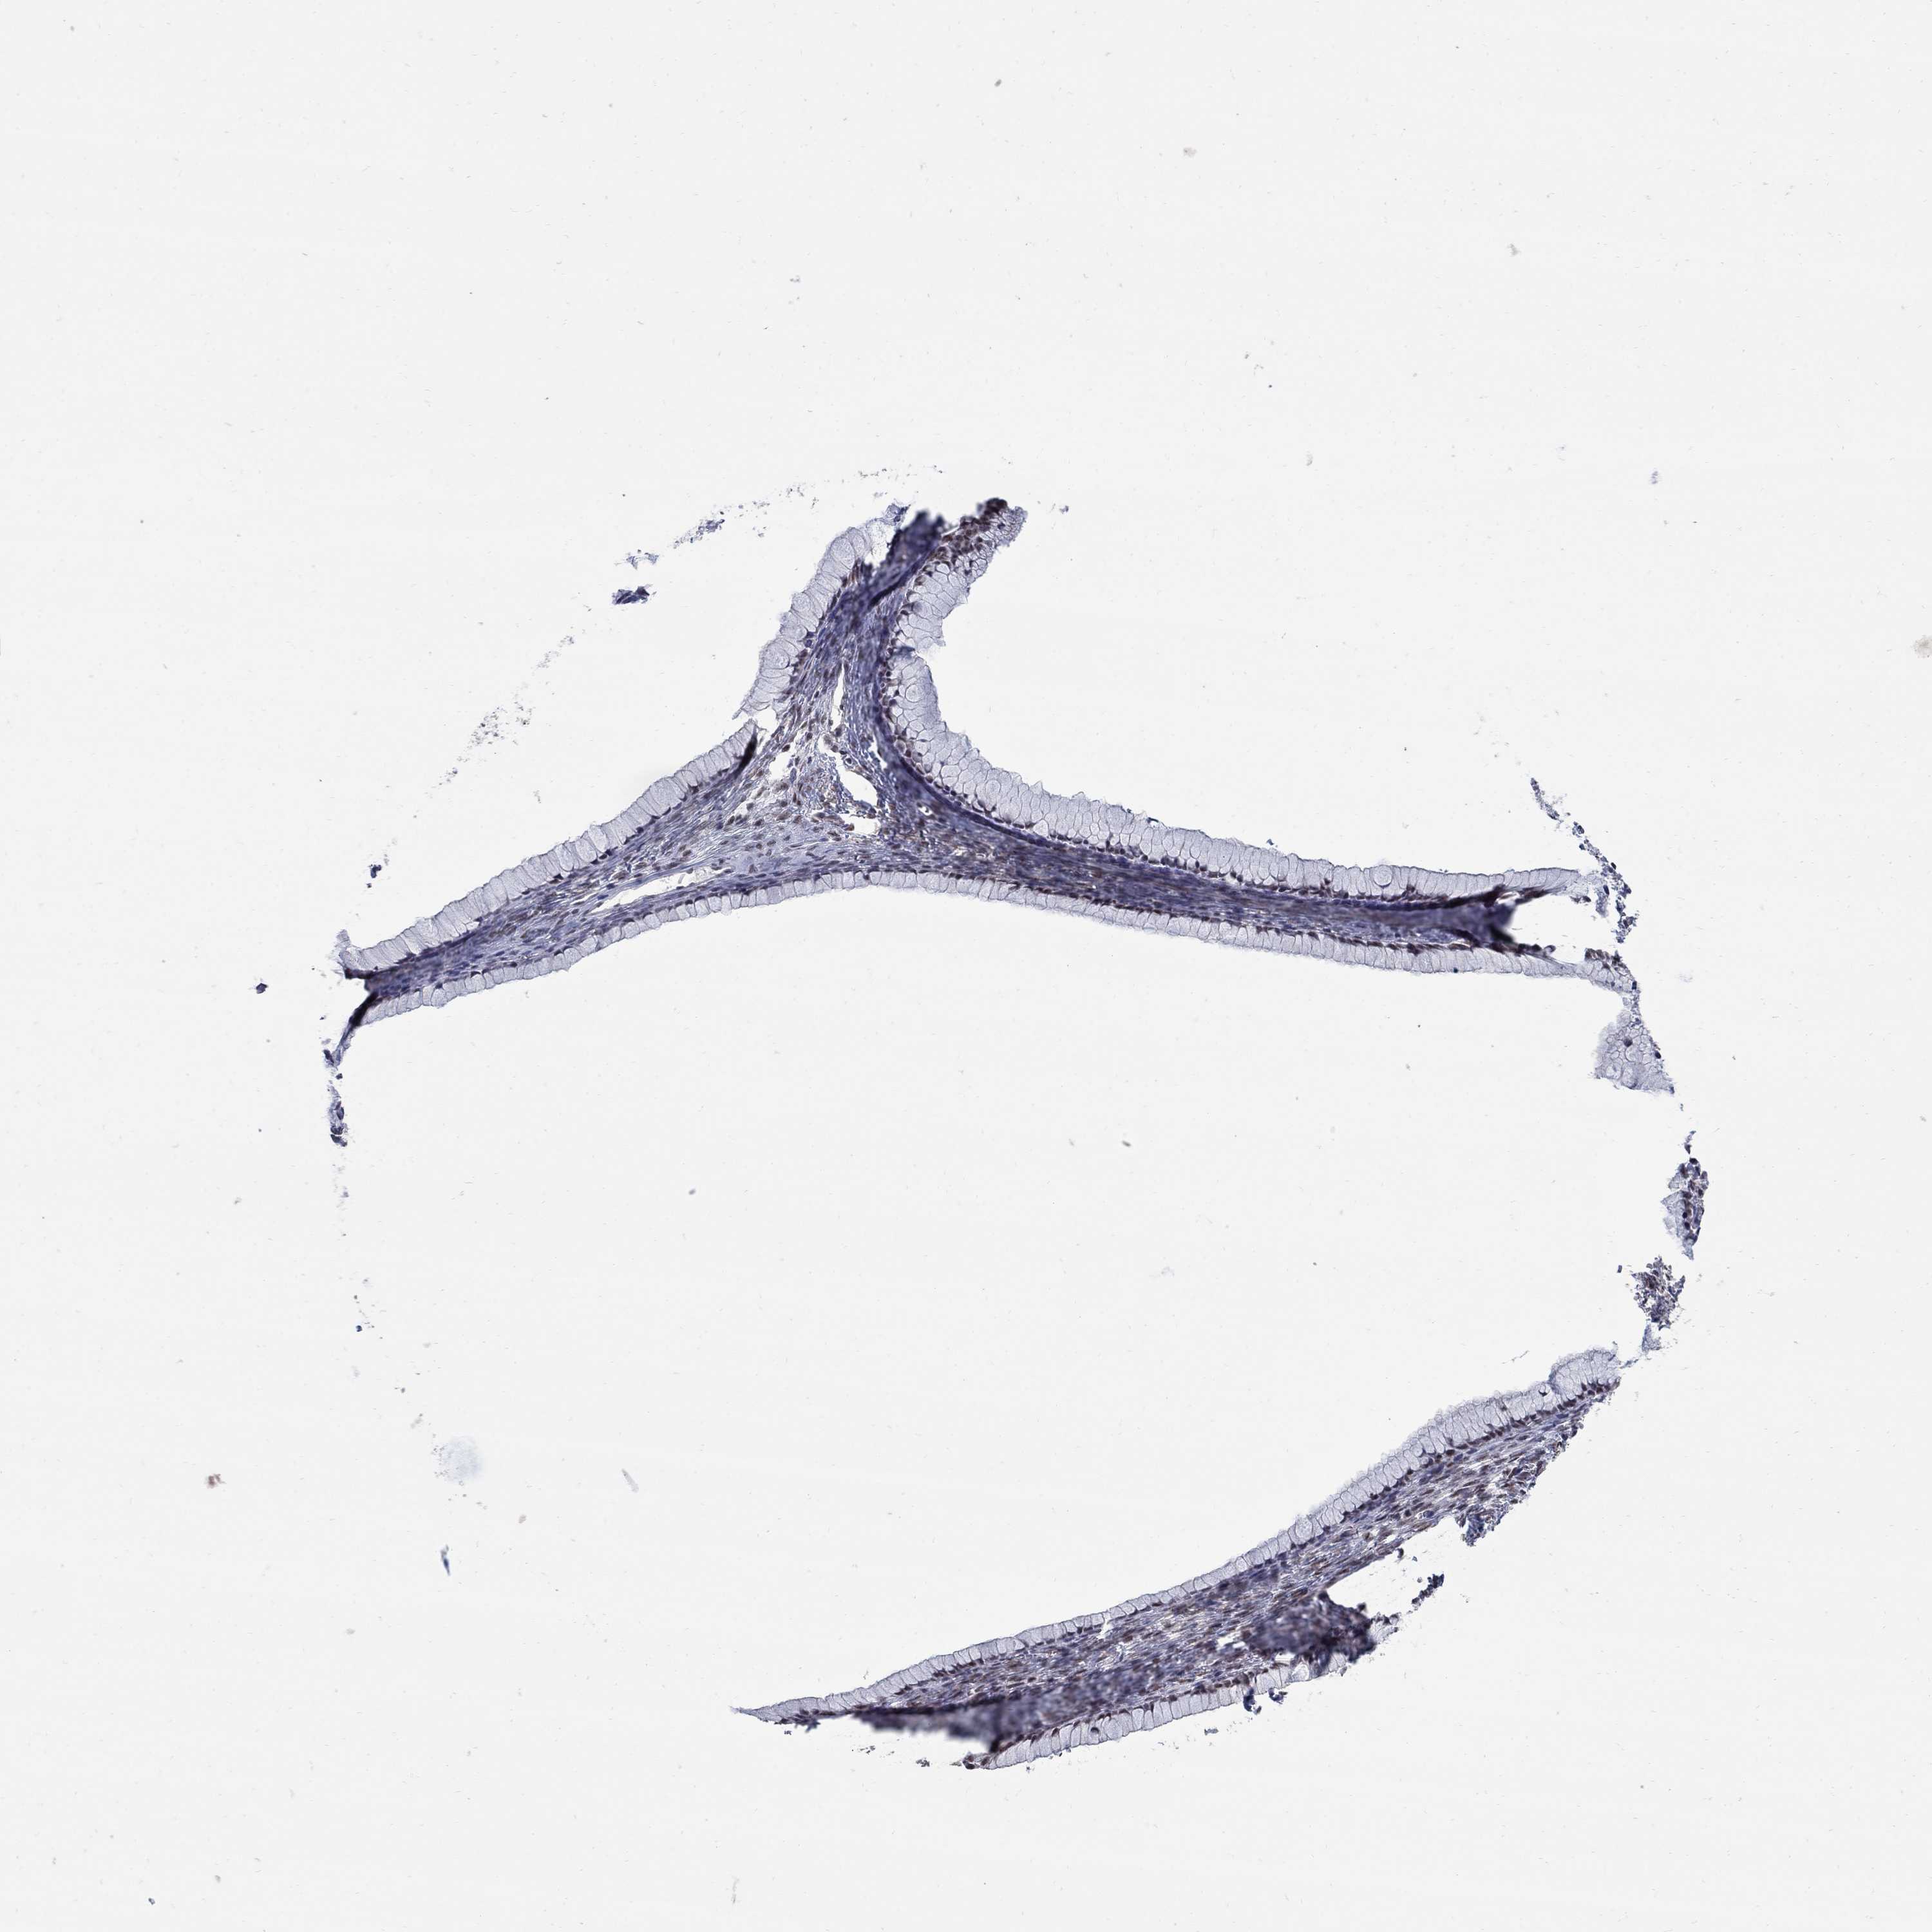

OVARIAN CANCER - Protein expressioni

A mouse-over function shows sample information and annotation data. Click on an image to view it in a full screen mode. Samples can be filtered based on level of antibody staining by selecting one or several of the following categories: high, medium, low and not detected. The assay and annotation is described here.

Note that samples used for immunohistochemistry by the Human Protein Atlas do not correspond to samples in the TCGA dataset.

Antibody stainingi

Antibody staining in the annotated cell types in the current human tissue is reported as not detected, low, medium, or high, based on conventional immunohistochemistry profiling in selected tissues. This score is based on the combination of the staining intensity and fraction of stained cells.

Each image is clickable and will lead to virtual microscopy that enables deeper exploration of all samples and also displays staining intensity scores, fraction scores and subcellular localization as well as patient and tissue information for each sample.

Antibody HPA075076

Staining

High

Medium

Low

Not detected

Intensity

Strong

Moderate

Weak

Negative

Quantity

>75%

75%-25%

<25%

None

Location

Nuclear

Cytoplasmic/membranous

Cytoplasmic/membranous,nuclear

Cystadenocarcinoma, serous, NOS

Cystadenocarcinoma, mucinous, NOS

Carcinoma, endometroid